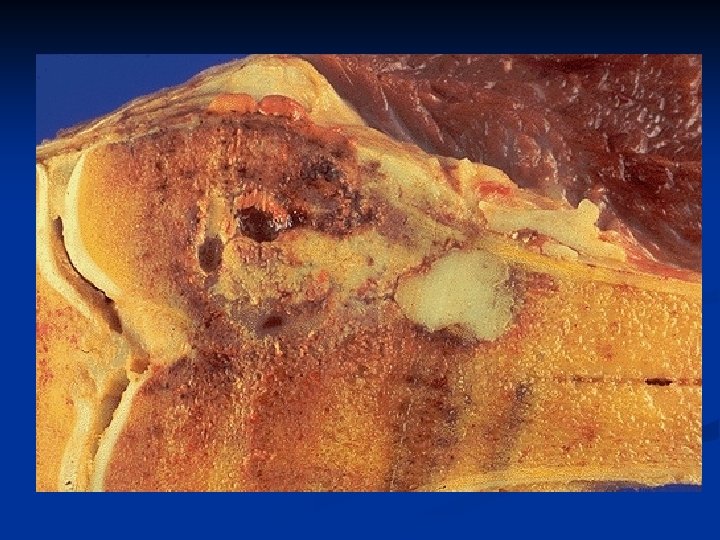

Osteosarcoma

Microscopy n Proliferating malignant spindle- cell stroma n Osteoid or immature bone